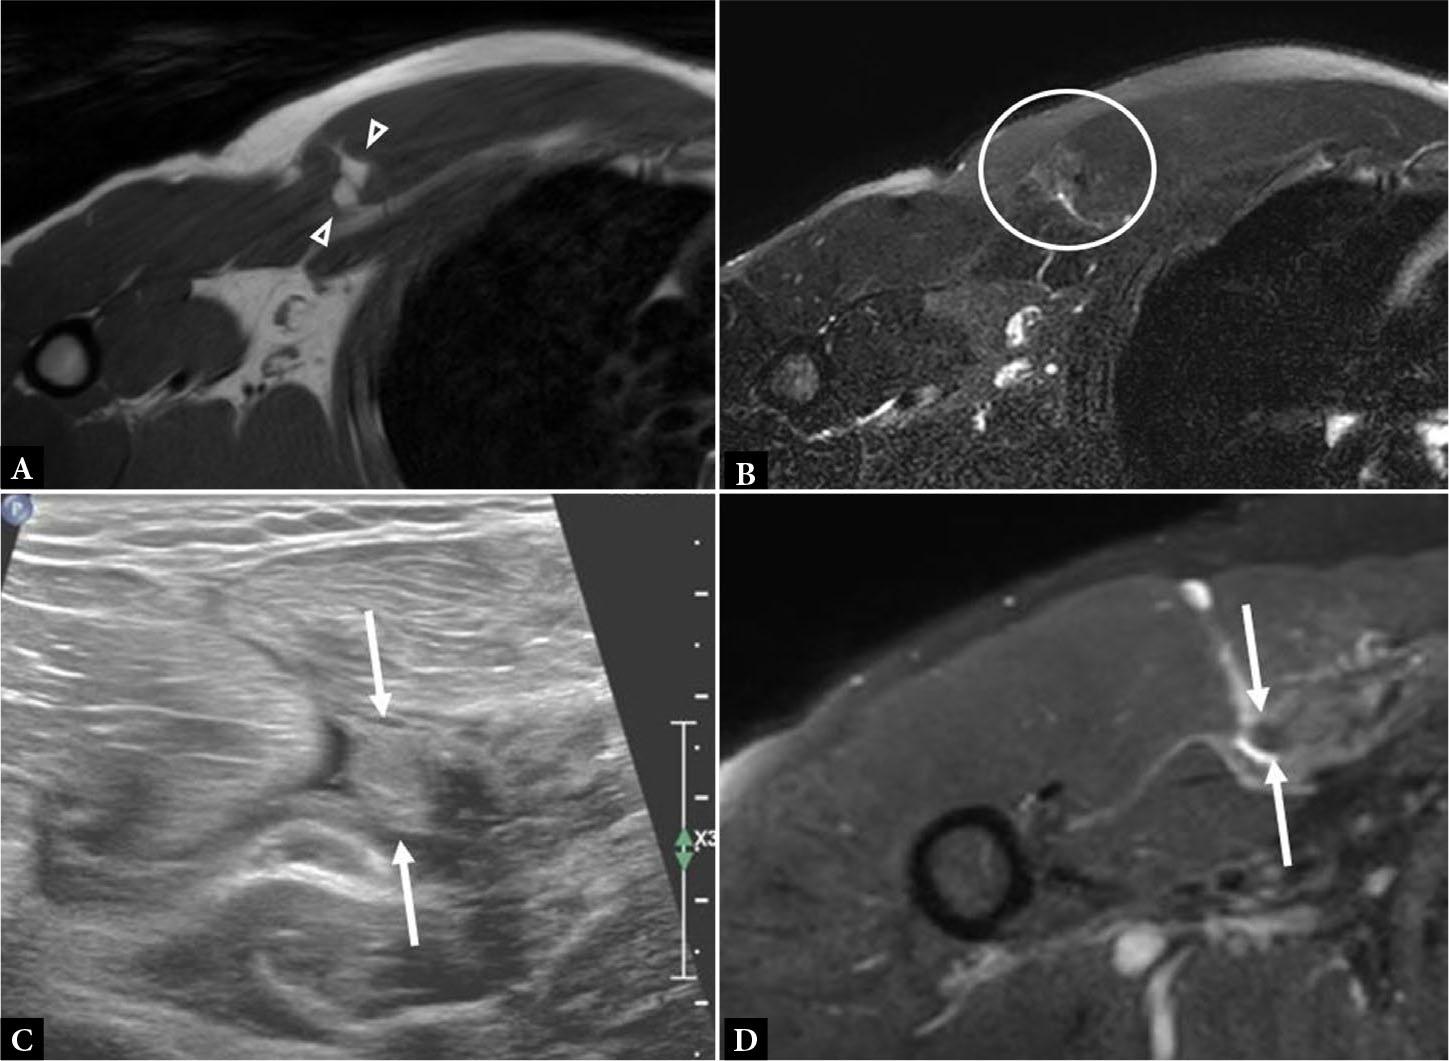

Fig. 13.

Axial T1 (A) and axial fluid-sensitive (B) MR images show focal fat at site of discontinuous muscle fibers (A, between arrowheads) from a chronic tear. Note the paucity of associated edema on the fluid-sensitive sequence (B, circle). C. Short axis gray scale ultrasound image shows a thickened and retracted torn PM tendon stump medially (between arrows). D. Corresponding MR image shows the retracted tendon stump (between arrows) with relative paucity of surrounding edema in this patient with chronic PM tear. Fibrosis was confirmed intraoperatively, which can also be seen with chronic tears

Full-thickness tears at the distal humerus insertion result in nonvisualization of PM tendon fibers superficial to the long head biceps brachii tendon which may be anteriorly displaced(8,10) (Fig. 9). Care must be taken on image interpretation to accurately identify the anterior and posterior layers of the PM tendon so that full width partial thickness tears are not misdiagnosed as completely intact tendon (Fig. 10).

Periosteal reaction can be detected on US in the setting of PM tendon injury (Fig. 10 D). MRI offers the additional benefit of detecting bone marrow edema which can be a secondary sign of injury (Fig. 11)(10). Radiography is beneficial in detecting periosteal reaction and osseous avulsion fracture (Fig. 12).

Findings of chronic PM injury include scar tissue formation, muscle atrophy, and tendon retraction (Fig. 13). A relative paucity of edema surrounding the PM tear is another characteristic of chronic injury.